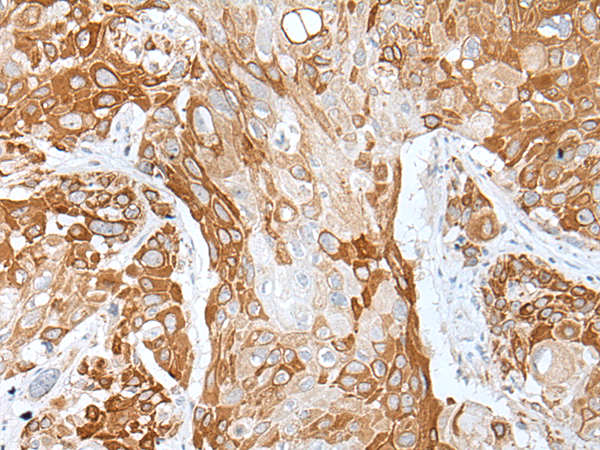

Immunohistochemistry of paraffin-embedded Human esophagus cancerwithDAPK1 antibody diluted at 1:20